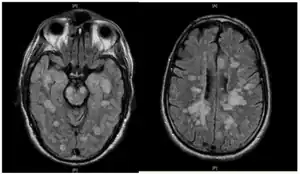

Fulminating ADEM showing many lesions. The patient survived, but remained in a persistent vegetative state | |